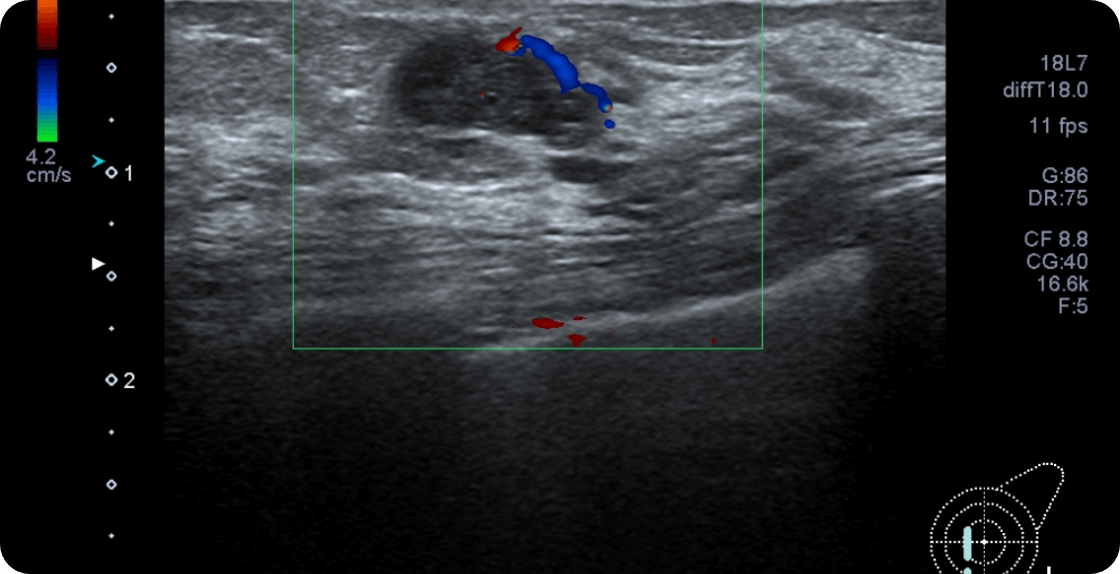

乳腺嚢胞

乳腺嚢胞(乳腺のう胞)とは、乳管が拡張し中に液体が溜まることが原因で起こる疾患です。乳腺症がベースにあり、のう胞を形成することもあるのでしこりや痛みといった症状を伴うこともあります。無症状の人の検診でもおよそ20~30%に見られる疾患です。

がん化することはありませんので基本的に治療は行わず、経過観察も不要のため無処置でよいです。以下の状況によっては、針を刺し液体を抜く治療処置を行うことがまれにあります。